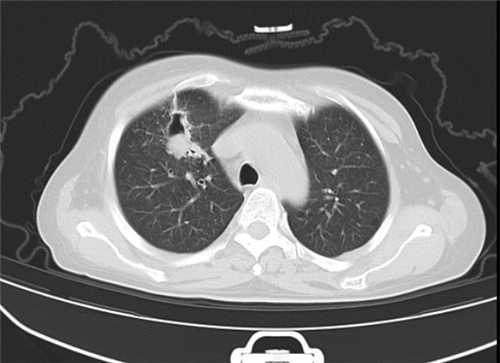

图1、2、3分别为抗真菌治疗前、治疗后和手术后的肺部CT检查影像。

让一家人没有想到的是,酒席结束后不久,顾女士出现了气促、胸闷、咳嗽、食欲下降、不能平躺的症状,甚至出现了濒死感。张丽华副主任医师立即为其安排了肺部CT检查,发现她的右上肺有一个8cm大小的肿物。为了明确诊断,顾女士接受了肺部纤支镜检查,检查结果让大家倒吸一口凉气,肺泡灌洗液检测结果显示,她的肺部多种细菌感染,其中最主要的为肺毛霉菌感染,而肺毛霉菌感染的死亡率极高。

所幸通过努力,顾女士肺部病灶缩小到2CM,迎来5月22日的手术机会。由胸外二病区主任周亚夫主刀,顾女士接受了右上肺叶切除术。肺毛霉菌感染导致肺易出血的倾向,反复炎症导致的肺门结构瘢痕化,肺动脉与支气管之间粘连严重,分离困难,手术团队巧妙地在腔镜下运用解剖剪做锐性分离,最终在3cm切口的单孔胸腔镜下顺利地切除病肺,术中失血小于100ml,术后顾女士第二日即下床活动,术后3日内顺利拔除胸腔引流管转回风湿免疫科。